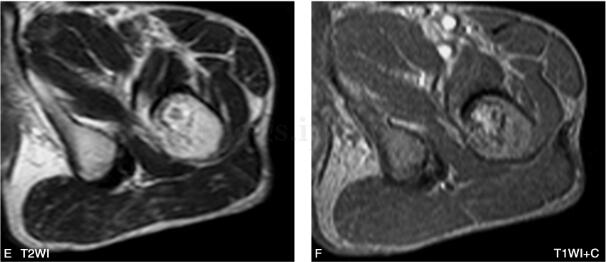

男,53岁,左髋部不适感1年余(图1~3)。

图3 MR:左侧粗隆间可见类圆形异常信号改变,边缘环形低信号,其内信号

(三)MRI

MRI能通过任意断面显示病灶和髓腔分隔,更清晰显示周围软组织受累的情况,而且能通过病灶信号特点评价其病理成分。病灶T1WI多呈低至等信号,而T2WI信号变化较大,病理结果显示,T2WI呈现高信号的病灶比低信号者有更少的骨小梁、更少的细胞成分及胶原纤维。由于骨纤在病变的不同阶段可有不同的病理改变,如病灶内存在较多囊变及坏死液化,则在T1WI呈低信号,在T2WI呈高信号。而病灶内的出血、软骨岛、残存的骨髓脂肪等成分,则在T1WI和T2WI均呈高信号。病灶内的钙化和周边的硬化在T1WI和T2WI均呈明显的低信号。增强扫描病灶可见不同程度的强化,这是因为在病灶的中心有较多小血管而且周边有大量的血窦,同时表明病灶代谢活跃。